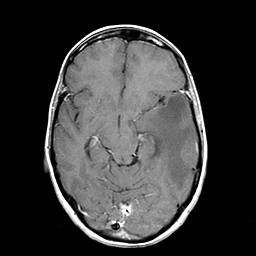

Metastatic bronchogenic carcinoma: T1-weighted MR -- Slice #9

[Home][Help][Clinical] Slice 9